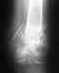

16.07.2015 был перелом левой пяточной кости с незначительным смещением. прилагаемый снимок сделан 20.07.2015 перед наложением гипса.

В больнице сказали категорически консервативное лечение. Проконсультировался еще с несколькими специалистами: 50% за операцию и 50% против. Причем те, кто против, против категорически, "ни в коем случае". те, кто за, угрожают в случае консервативного лечения проблемами при реабилитации и болями в будущем, невозможностью бегать и прыгать, ранний артроз. Те же, кто против, считают, что смещение минимально, проблем от операции может быть ОЧЕНЬ много, вплоть до остеомиелита, кость без операции будет после восстановления почти, как "до", проблем с бегом даже не будет. Подскажите, пожалуйста, чем обусловлены в данном случае обе точки зрения, и каково Ваше мнение?

Чем обусловлены разные взгляды - это слишком много рассказывать. Действительно, при таком положении фрагментов шансы, что все будет приемлемо, высокие. КТ надо сделать на всякий случай.